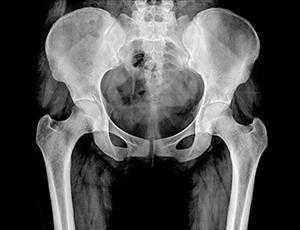

Рентген костей таза

Таз представляет собой часть скелета, которая расположена в основании позвоночного столба. Он не только является опорой для внутренних органов, но и обеспечивает фиксацию к туловищу ног. Именно поэтому его здоровье играет немаловажную роль, а рентген костей таза является неотъемлемой составляющей диагностики при заболеваниях и травмах этой области.

Он является диагностическим высокоинформативным методом, позволяющим получить данные о состоянии костных структур и суставов таза, определить повреждения и патологии мягких тканей и внутренних органов. Рентгенографию широко применяют в поликлиниках, поэтому она является доступным методом, в том числе и в ценовом плане. Пройти рентген костей малого и большого таза можно в диагностическом центре многопрофильной клиники ЦЭЛТ. Мы располагаем современным оборудованием, а наши специалисты практикуют индивидуальный подход, что неизменно позволяет добиваться высокого качества рентгенографических снимков.

Диагностику проводят исключительно по назначению врача при наличии клинических проявлений, которые свидетельствуют о следующих патологических изменениях тазовых костей:

- Трещины, гематомы, ушибы, переломы, вывихи;

- Снижение плотности костных структур (остеопороз);

- Аномалии развития;

- Подвывихи и вывихи бёдер;

- Поражения суставов инфекционной природы, а также вследствие нарушения обменных процессов организма;

- Новообразования добро- или злокачественной природы;

- Метастатические очаги при новообразованиях, расположенных в других местах;

- Оценка эффективности лечебной тактики и необходимости её коррекции.